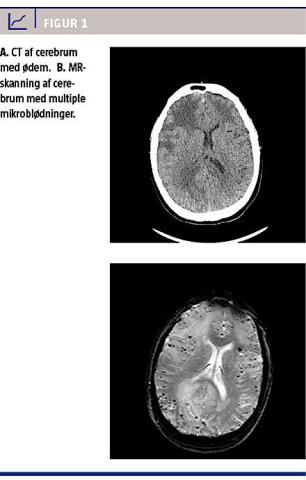

Objektivt fandt man forlænget psykomotorisk latens, venstresidig hemianopsi og hemiparese samt venstresidigt neglect. CT af cerebrum viste asymmetrisk udbredt hvid substans-ødem med massevirkning i begge hemisfærer. Der var udslettede overfladefurer, klemt lateralventrikel og klemte basale cisterner samt en midtlinjeforskydning på 1 cm. I løbet af første indlæggelsesdøgn blev patientens kliniske tilstand forværret. Han kunne vækkes på tiltale, svare ja og nej, men faldt ustimuleret hen. Der blev forsøgt akut MR-C, der måtte opgives pga. motorisk uro hos patienten. I stedet blev der foretaget en CT med kontrast af cerebrum, hvor man fandt uændret ødem, og ingen opladning.

MR-C på fjerdedagen viste let aftagende vasogent ødem og ingen opladning. Desuden fandt man på T2*-sekvensen utallige punktate blødningsfølger beliggende kortikomedullært i alle lapper. Patienten blev udskrevet i habitualtilstand 14 dage efter indlæggelse. En kontrol MR-C ca. tre måneder senere viste fuldstændig regression af ødem og massepåvirkning. De følgende måneder var han velbefindende, og der blev initieret langsom prednisolonnedtrapning. Ca. 1 år efter indlæggelsen fik han på ny kognitiv påvirkning. Der blev foretaget MR-C, der viste flere nytilkomne højsignalsforandringer perifert og subkortikalt bilateralt med massevirkning. Han fik øget prednisolondosis med god klinisk effekt og regression af ødemet.

følgende: hovedpine, bevidstheds- eller adfærdsændringer, fokale neurologiske udfald eller anfaldsfænomener. Samtidigt skal der kunne ses karakteristiske forandringer på MR-C. På blodfølsomme sekvenser ses multiple kortikale eller subkortikale mikroblødninger og eventuelt tidligere lobær blødning som udtryk for CAA sammen med pletvise eller konfluerende hvid substans-hyperintensiteter på fluid attenuated inversion recovery og T2-vægtede sekvenser. Hvid substans-forandringerne er ved CAA-I hyppigst asymmetriske og kan have betydelig masseeffekt. Der er typisk ikke kontrastopladning, hvilket kan være med til at differentiere denne tilstand fra cerebrale tumorer. Infektiøse og neoplastiske årsager skal udelukkes. For at stille en definitiv diagnose skal der være en cerebral og en leptomeningeal biopsi med amyloidaflejring med perivaskulær, transmural og/eller intramural inflammation [3].